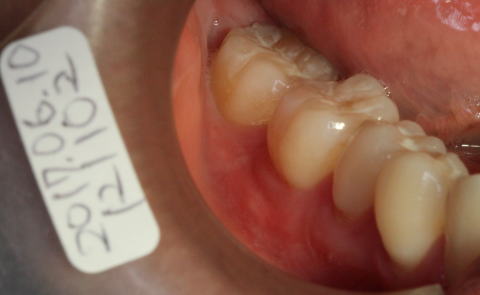

2017-04-19 初診 主訴:左下臼歯部がしみる。またくさび状欠損がある。歯ぐきの退縮。 治療方法 20代で、歯ぐきの退縮が認められる。 このままでは、将来的に歯ぐきや骨欠損による歯槽膿漏で歯が抜けてくるので、造骨と歯肉弁歯冠側移動術を提案。 |

2017-06-10 術後約1.5カ月後 歯ぐきの形も、自然治癒で、きれいに整っています。 |